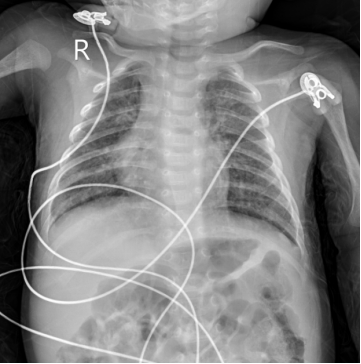

1、诊断方法:沙眼衣原体肺炎的诊断,除依据上述临床表现,还需完善痰液、鼻咽拭子病原学核酸、胸片等关键检查。其中,痰液、鼻咽拭子病原学核酸检测是诊断金标准,胸片检查常显示肺部过度充气和弥漫性肺间质浸润。